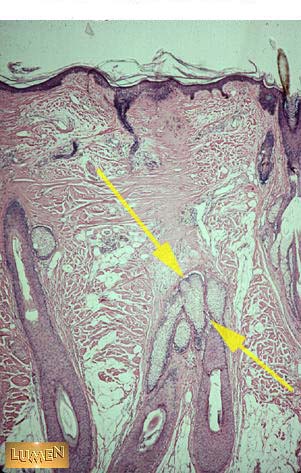

Identify this structure. Be specific.

Sebaceous glands.